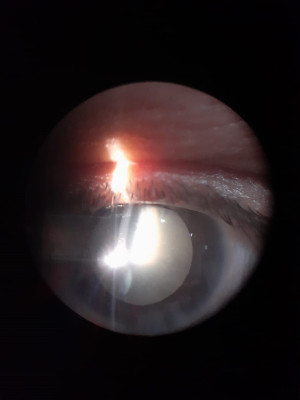

Casos Clínicos

Envíado por Dr. José Alfredo Martínez